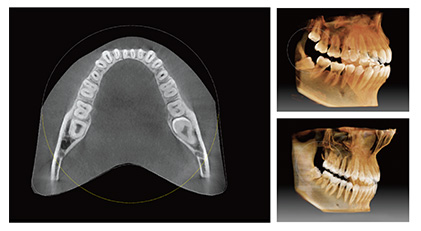

一次扫描,两张影像

一个绿色智能的扫描不仅可以给你一份CT图像,还可以有一张全景效果的影像。这意味着患者不需要进行两次X光扫描。

智能全颌弓扫描是根据颌弓的弓形进行扫描,一次扫描即可获取整个颌骨的牙齿,并包括第三磨牙。